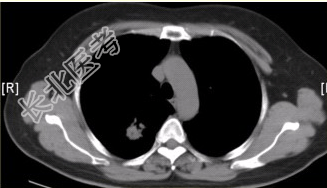

- [材料题] 患者女,54岁,无症状,常规体检透视时发现右上肺阴影。既往无结核病史。体格检查阴性。CT结果如下图。

- 多项选择题1.本病例可见的征象包括

A、分叶征

B、毛刺征

C、胸膜凹陷征

D、空泡征

E、含气支气管征

F、钙化